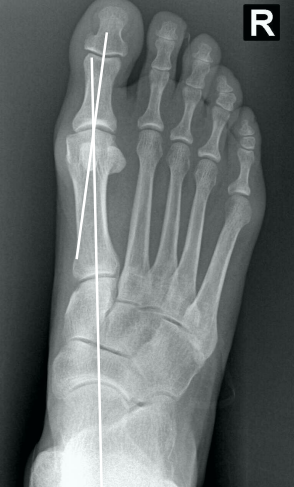

• Como verificar na radiografia AP com carga, se há luxação do sesamóide e classifica-lo de acordo com Mann e Coughlin?

A

• Traça-se um linha no eixo do 1° mtt e verifica o quanto, em “%”, a linha toca o sesamóide tibial (medial)